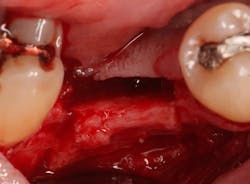

An osteotomy was then created, extending to the apical portion of the split ridge in preparation for implant placement. A bone-level tapered 4.1- x 12-mm implant was placed with a flat cover screw. A mixture of cancellous and cortical allograft particulate was infused with autogenous PRGF and packed around the implant on the mesial and distal aspects. The newly out-fractured buccal plate was positioned intimately adjacent to the buccal portion of the implant, and additional graft material was placed over the buccal plate to further augment the bone horizontally and reduce the risk of buccal-plate resorption during healing. A 25- x 30-mm Ossix Plus membrane was soaked in saline for three minutes and trimmed to extend 3–4 mm beyond the confines of the bone graft and roughly 1 mm from the adjacent teeth.

After the photo was taken to demonstrate the membrane placement, a periosteal elevator was used to further push the membrane under the lingual flap so that it draped intimately over the graft. The partial-thickness flap preparation made during initial incisions allowed for coronal positioning for tension-free primary closure. A CV-5 horizontal mattress suture was used to bring the buccal and lingual flaps together, and closure was completed with interrupted sutures.